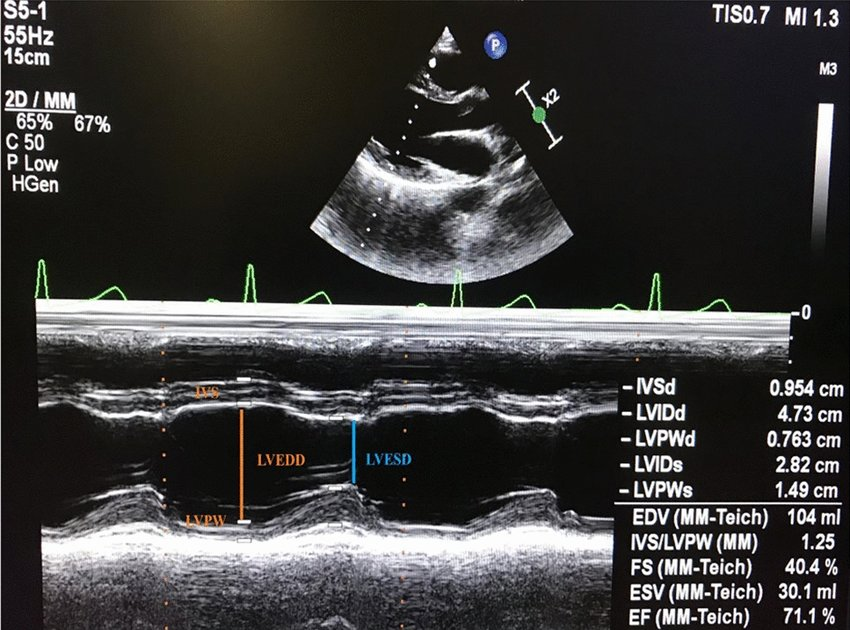

Explain the purpose of using M-mode.

precise recording of the position and motion of cardiac muscle, valves, and surrounding tissue

measurements can be compared against normal values

What is represented in the x and y axis of M-mode

x axis - time

y axis - depth

Name the primary limitation of M-mode.

If the M-mode line is not perpendicular with the anatomy, the measurement will be inaccurate

In an M-mode tracing of LV basal wall in PSLAX, list the measurements made and describe how to measure them

LV basal wall

cursor just past the mitral valve leaflets

IVS measured at end diastole from the right to left surfaces of the IVS

LVIDd measured at end diastole from the tissue edge of anteroseptal interface to tissue edge of inferolateral interface

Inferolateral wall diameter measured in end diastole from the endocardial surface to epicardial surface of the posterior wall

LVIDs measured at end systole from the tissue edge of anteroseptal interface to tissue edge of inferolateral interface

Normal value for LVIDd

W: 3.8 - 5.2cm

M: 4.2 - 5.8cm

Normal value for LVIDs

W: 2.2 - 3.5cm

M: 2.5 - 4.0cm

Normal value for IVS wall thickness

W: 0.6 - 0.9 cm

M: 0.6 - 1.0 cm

Normal value for posterior wall thickness

Name the two methods for calculating LV volumes from LV linear dimensions. Why are these not recommended for clinical use?

Teichholtz Method

Guinones Prolate Ellipsoid Method

Both rely on the assumption that the LV is a fixed geometric shape (prolate ellipse) - inaccurate assumption for many cardiac pathologies

Normal range for LV EF%

W: 54 - 74%

M: 52 - 72%

Normal range for FS

25 - 45%